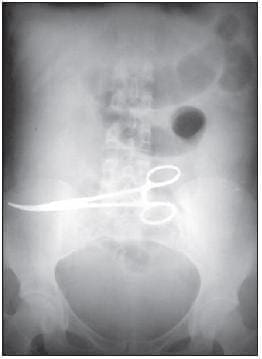

En la endoscopia digestiva alta se observó lo que podría corresponder a un cuerpo extraño, por lo cual se le solicitó –por interés académico– una radiografía simple de abdomen que mostró una imagen radiopaca plegada en la línea media (material radiopaco de compresa), con lo cual se hizo el diagnóstico de cuerpo extraño. Fue sometida a cirugía (figura 2).

FIGURA 2. Radiografía simple de abdomen con imagen radiopaca plegada en la línea media.